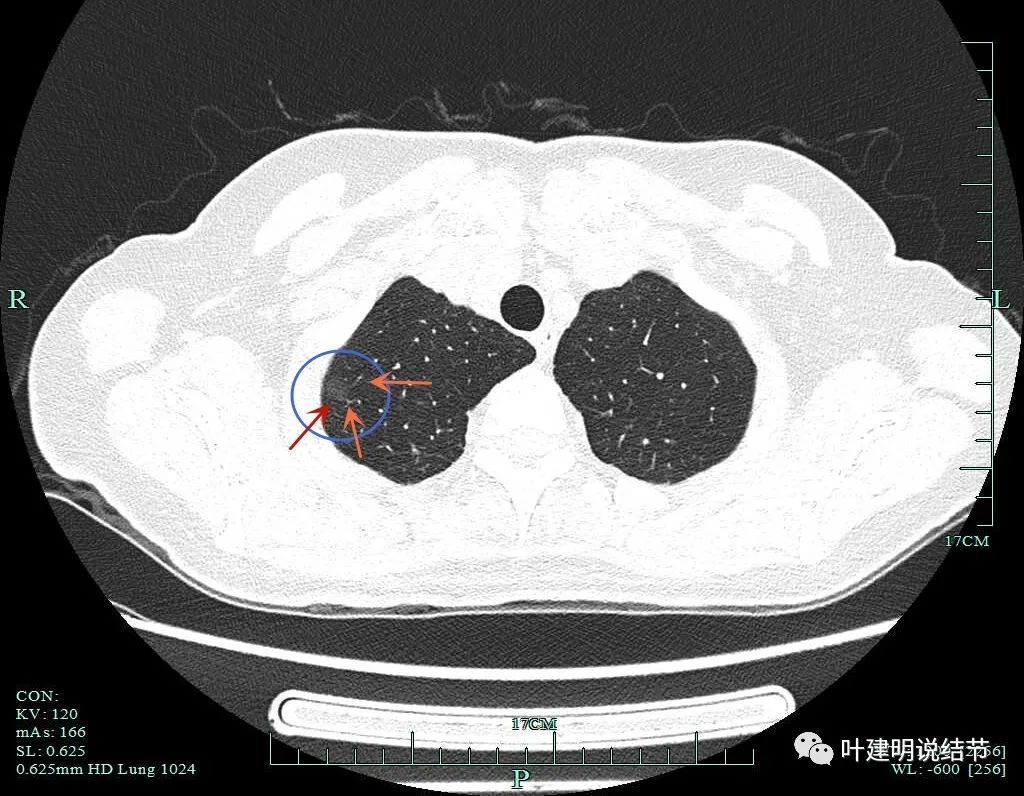

病灶1:右肺尖淡磨玻璃结节,微小而轮廓较清,考虑肺泡上皮增生可能性大,风险低,能随访。

病灶2:右肺尖淡磨玻璃结节,有微小血管进入,轮廓与瘤肺边界清,从密度看不典型增生可能性大,但因有微血管,升一级考虑,所以有原位癌可能性,近期风险不高,可随访。

病灶3:右肺上叶尖段微小磨玻璃结节,约2毫米,在病灶2附近,考虑肺泡上皮增生可能性大,风险低,能随访。

病灶8:右下叶磨玻璃结节了,轮廓清,血管贴边,边缘显毛糙。

有明显小血管进入,小血管有异常增粗。从密度考虑不典型增生可能性大,但因血管进入升一级考虑,原位癌可能性大点。如果没有上叶病灶6存在,此灶可随访,近期风险不算高。

病灶6重建后显示血管进入与穿行。

病灶2重建后显示瘤肺边界清以及血管进入。

病灶8重建后显示血管与结节间没有间隙,而且瘤肺边界很清。